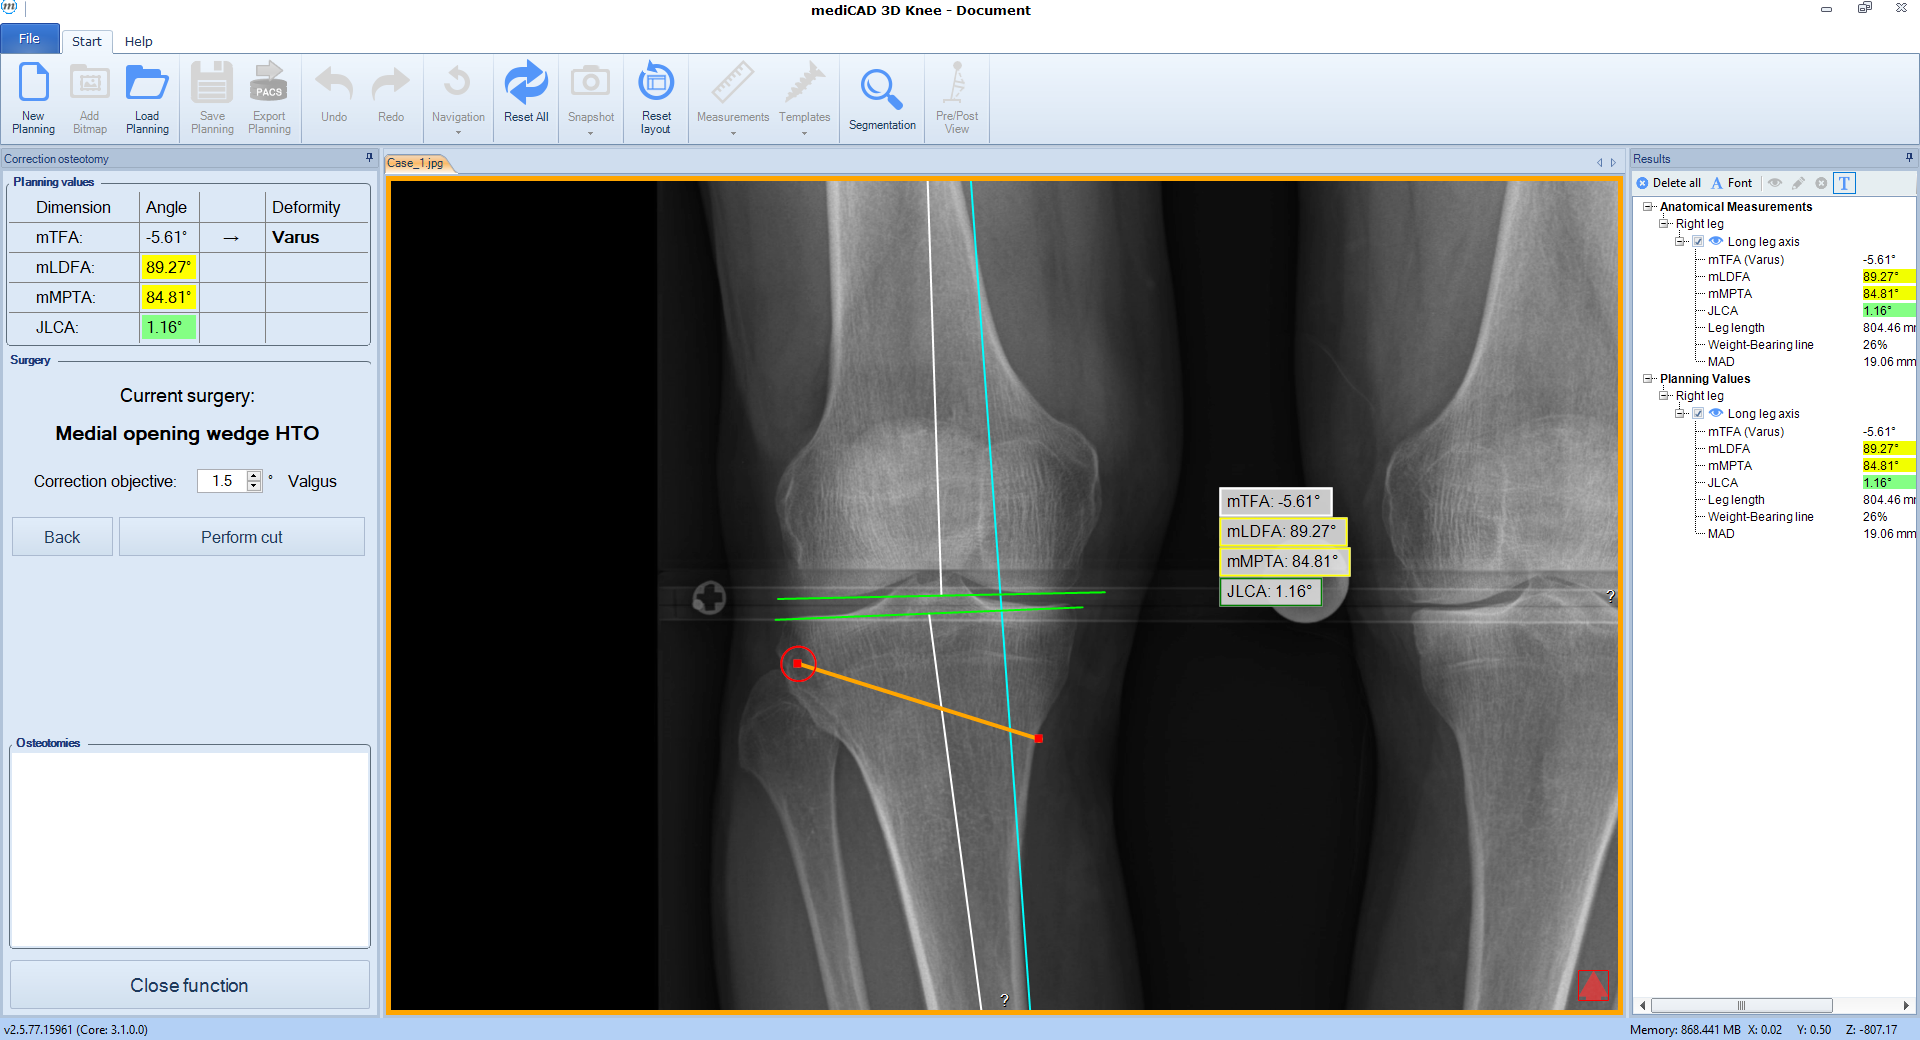

Once the procedure is selected, the software automatically places the cutting line and hinge point for the chosen osteotomy adapted to the individual anatomical condition (Fig 3).